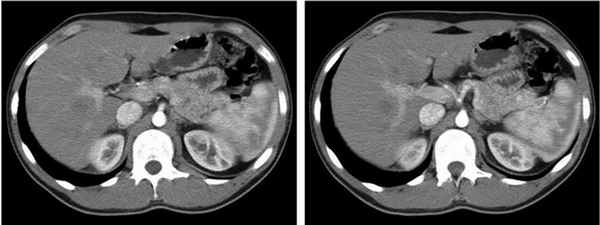

УЗИ: в области перешейка и тела ПЖ обнаружено 5 опухолей диаметром от 12 до 5 мм. Эндоскопическая ультрасонография радиальным датчиком: в области перешейка ПЖ - опухоль диаметром 16 мм, в теле и хвосте - опухоли диаметром 9 и 8 мм. КТ: гиперденсное образование в теле ПЖ размером 14×11 мм, в головке - 12 мм, два образования в хвосте ПЖ размерами 17 и 12 мм (рис. 1). Рисунок 1. Мультидетекторные спиральные компьютерные томограммы больного К. Множественные инсулиномы в теле (а) и хвосте (б) поджелудочной железы.

При УЗИ брюшной полости патологических изменений не выявлено. УЗИ щитовидной железы: узел размером 18×13 мм в правой доле, неоднородной структуры. Больная консультирована эндокринологом, рекомендована диагностическая пункция узла в плановом порядке после оперативного вмешательства на ПЖ. При эндоскопическом УЗИ радиальным датчиком заподозрено очаговое образование в области хвоста ПЖ до 10 мм в диаметре. МД-СКТ брюшной полости и головного мозга: гиперденсное образование по переднему контуру хвоста ПЖ размером 16×10 мм (рис. 2), Рисунок 2. Мультидетекторная спиральная компьютерная томограмма больного К. Инсулинома хвоста поджелудочной железы (стрелка). размер аденомы гипофиза 10 мм. МРТ брюшной полости: патологических изменений не выявлено.